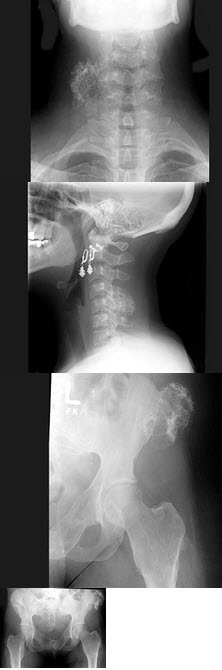

16、多项选择题

男,64岁,进食梗阻感半月。体检:咽充血少许滤泡,结合图像,最可能的诊断为()

A.会厌征

B.颈椎退变

C.食管癌

D.食管型颈椎病

E.以上都不是

23、单项选择题 肾盂积水的影像改变,最早出现在()

D.骨巨细胞瘤

A.内踝

男,根据其正常盆腔影像图像,判断其最可能的年龄()

A.10岁左右

B.30岁左右

C.20岁左右

D.80岁左右

E.60岁左右